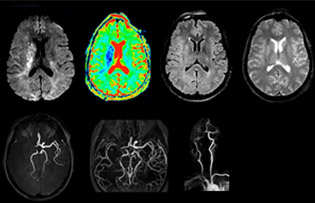

Every minute counts in stroke imaging

“In France, stroke is usually imaged with MRI, not CT, even for emergency treatment. This is because MRI helps us directly visualize ischemia in the acute phase, but can also help rule out differentials such as MS and hematoma. In addition, we can assess the intracranial and extracranial vessels during the same examination,” says Dr. Savatovsky.

The first challenge in MRI of stroke is speed. The patient typically arrives from an ambulance in the MRI preparation room and the installation is done on a separate dock outside the scanner room. “The venous access is placed during the neurological examination. If the delay from the first symptoms allows the patient to receive thrombolysis we do a very fast examination that typically lasts about 11 minutes including the pre-scans. In the case of transient ischemic stroke we usually add ASL perfusion because in some symptoms with negative diffusion, ASL sometimes indicates a vascular origin.”

“Ingenia provides great flexibility in the parameters setting. We can tune a sequence the way we want,” says Dr. Savatovsky. “For example, in a stroke exam we use a FLAIR sequence of about two minutes instead of the four-minute FLAIR we use for MS. The diffusion is 30 seconds, the T2*-weighted scan is 30 seconds, the angiography scan time is less than one minute. Ingenia is a great scanner in that situation; even with these fast sequences we can achieve good images with good SNR. When the first sequence tells us that it’s not an ischemic stroke but a hemorrhagic stroke, we may switch to a time-resolved angiography to look for vascular malformations and venous thrombosis.

The ideal stroke protocol?

“Every center is different, but for me the ideal protocol for stroke includes diffusion weighted imaging, FLAIR, and fast susceptibility imaging,” says Dr. Savatovsky. “Our fast susceptibility weighted imaging takes 50 seconds, so it’s as fast as T2*-weighted imaging. It visualizes hemorrhage but also the clots. We also do 3D MR angiography that provides information on cervical and brain vessels. If the patient does not need immediate treatment, or if additional information is needed to decide on treatment, we might also add perfusion imaging and post-contrast T1-weighted imaging.”